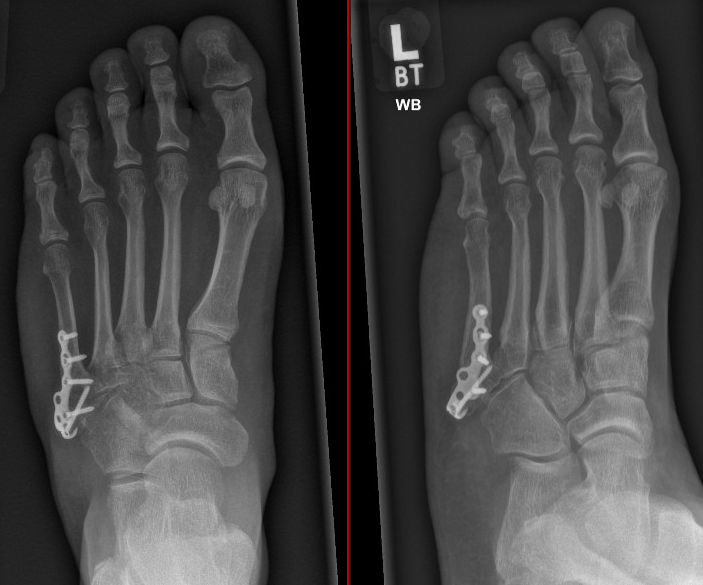

Figure 6: 3 months following revision fixation and cancellous autograft (from heel)